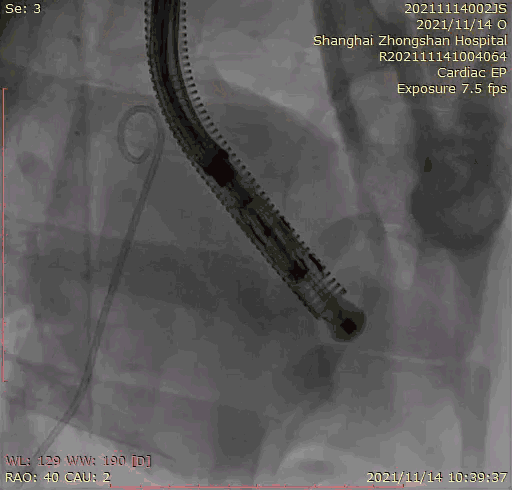

2021年11月14日星期日,復(fù)旦大學(xué)附屬中山醫(yī)院(以下簡稱中山醫(yī)院)葛均波院士團(tuán)隊(duì)成功應(yīng)用經(jīng)血管介入三尖瓣置換產(chǎn)品Lux-Valve Plus完成臨床前研究,并獲得圓滿成功!此次研究的成功預(yù)示經(jīng)血管三尖瓣產(chǎn)品Lux-Valve Plus已完成臨床前準(zhǔn)備,即將開啟后期的正式臨床研究!

上海中山醫(yī)院葛均波院士、錢菊英院長、周達(dá)新教授、潘文志教授、潘翠珍教授、李偉教授共同完成此次臨床前研究。術(shù)后葛均波院士對Lux-Valve Plus的器械操作性能給予了高度評價,DSA和超聲影像也顯示出在本次研究中Lux-Valve Plus的安全性和有效性俱佳。

本次臨床前研究經(jīng)右側(cè)頸靜脈置入LuX-Valve Plus輸送系統(tǒng)可調(diào)彎鞘管,在DSA及超聲引導(dǎo)下將人工三尖瓣瓣膜植入到原有三尖瓣位置,利用獨(dú)特的錨定技術(shù)將人工瓣膜支架可靠固定在預(yù)定的位置。

Lux-Valve是全球第一款具有我國完全自主知識產(chǎn)權(quán)的經(jīng)導(dǎo)管介入三尖瓣置換系統(tǒng),利用前瓣夾持及室間隔錨定的復(fù)合方式進(jìn)行瓣膜裝置的固定,不依賴瓣環(huán)徑向支撐力,同時采用自適應(yīng)復(fù)合裙邊材料,有效的貼合密封柔軟的三尖瓣瓣環(huán),針對于三尖瓣返流的患者有優(yōu)異的療效。Lux-Valve Plus采用全新的經(jīng)血管輸送系統(tǒng),經(jīng)頸靜脈入路創(chuàng)傷更小,可以進(jìn)一步降低手術(shù)風(fēng)險。相信在后期正式臨床研究開展中,Lux-Valve Plus必定會為更多的三尖瓣反流患者帶來福音。